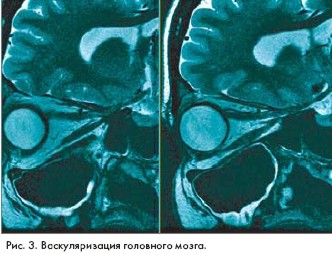

Магнитно-резонансные изображения (magnetic resonance imaging - MRI), полученные на основе высокоскоростного сканирования с помощью технологии GE Excite, открывают новые возможности хорошо известного метода исследования. Идея была представлена на 10-й научной конференции Международного общества Magnetic Resonance in Medicine, которая прошла в США.

Система GE Excite была разработана компанией GE Medical Systems (США). Высокая скорость сканирования и компьютерной обработки данных позволяет получать объемные MR-изображения высокого разрешения в реальном времени, например в процессе работы сердца.

"Мы впервые получили возможность получать изображения в процессе реальной жизнедеятельности органов, - говорит доктор Lawrence Tanenbaum из Института неврологии Нью Джерси (США). - GE Excite не требует задержки дыхания в процессе исследования больных и особенно удобна для получения качественных изображений органов, находящихся в движении, например сердца и сосудистой системы"